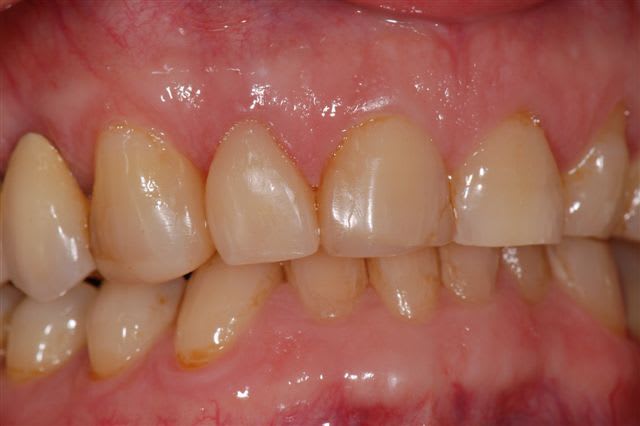

Souvenez vous, il y a 6 mois, je vous ai posté des photos sur un cas de parodontopathie aiguë localisée à la 12, voici les photos et radio 6 mois plus tard, après traitement de la paro au laser diode 980 nm sous bipivone puis H2O2, bio stimulation tous les 15 jours et reconstruction de la couronne en emax avec le CEREC 6 mois plus tard.

La couronne sur 12 est sympa.

Oui, belle gencive, collets toujours alignés et effectivement la couronne est bien maquillée.

Résultat clinique et radiologique plutôt encourageant à 6 mois.

Quelques remarques :

- Dommage que les radios ne soient pas indexées avec leur date, car avec le désordre dans lequel le serveur les met, c'est un peu plus difficile de suivre l'évolution de la guérison (qui n'est pas encore complète apparemment).

- J'espère que tu as bien évalué la vitalité pulpaire car celle-ci n'est peut être pas au top de son potentiel après tout ça.

- Voici 1 cas apparemment réussi à 6 mois. Le Cerec n'a rien à voir dans l'affaire, c'est juste un moyen comme un autre de faire une restauration coronaire. Le problème est celui du traitement parodontal par laser.